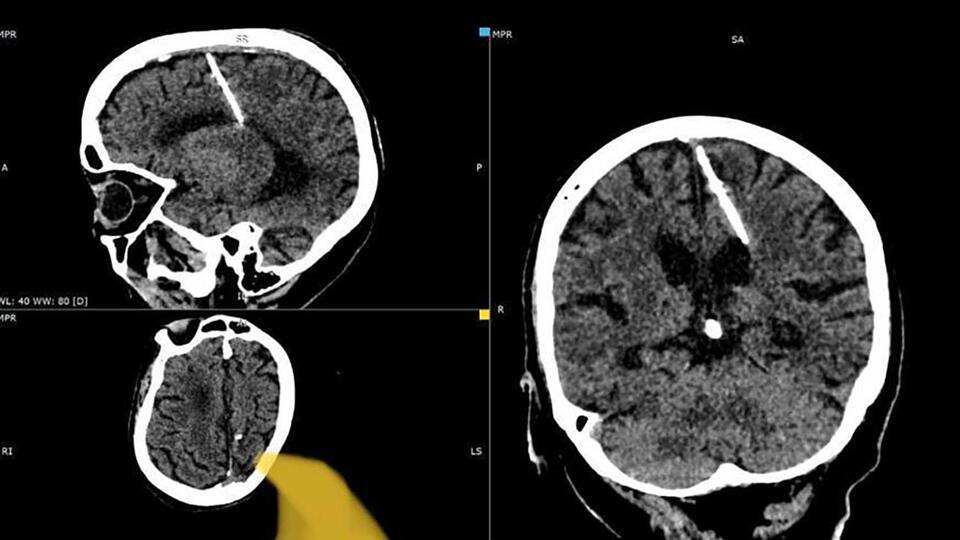

Жительница Сахалина прожила 80 лет с трехсантиметровой иглой в мозге и не жаловалась на самочувствие. Шокирующую находку на снимке компьютерной томографии обнаружили медики, когда обследовали бабушку совсем по другому поводу. Более того, пенсионерка даже никогда не мучали головные боли — редкий случай для её возраста.

"Здоровью пациентки ничего не угрожает, за её состоянием наблюдает лечащий врач. Оперативное вмешательство было принято не проводить, так как это может только ухудшить её состояние", — сообщили в Минздраве региона.

Причина, по которой игра попала в мозг россиянки, достаточно известна, но оттого не менее печальна. Именно таким образом — вгоняя игры в родничок — в сложные военные годы умертвляли новорожденных младенцев